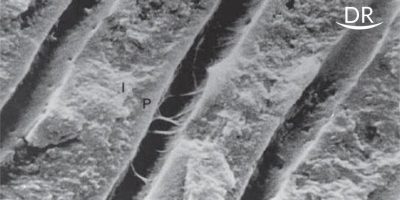

Continued Etching of Wet Dentinal Tubules by Single Bottle And Two Bottle Self Etch Adhesive-A Comparative In Vitro Study

One-bottle self-etching adhesives have been introduced that combine ... Limited research has been conducted comparing the efficacy ...